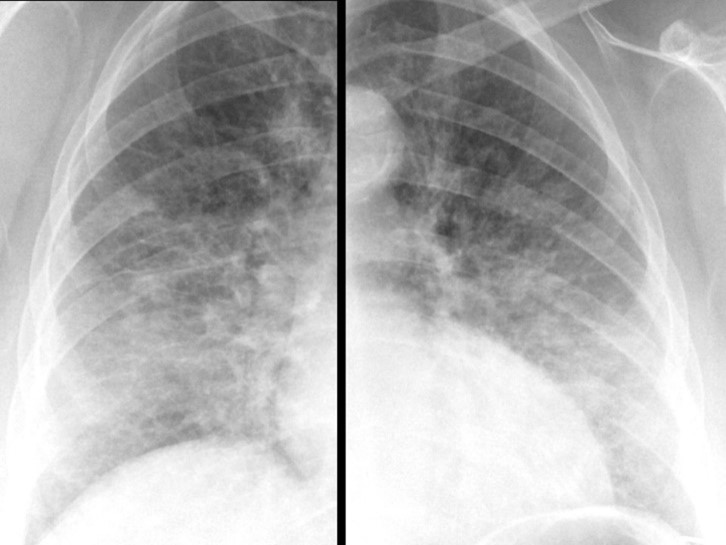

Radiografía de tórax PA en bipedestación